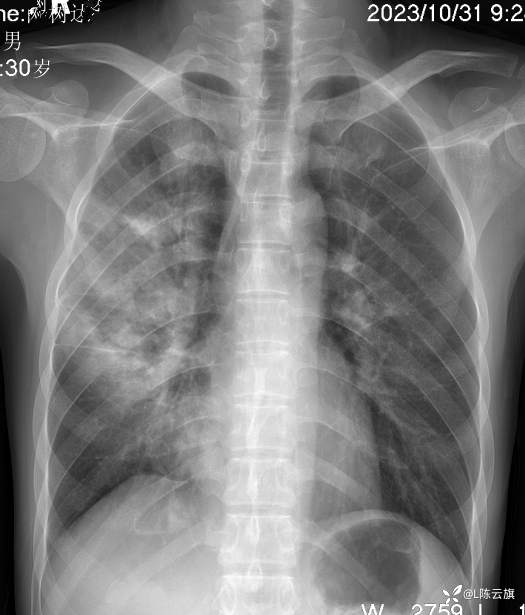

病例[每周胸片] 207 正侧位胸片 该如何诊断?(结果已公布)

患者男,30岁,精神病长期住院患者。咳嗽、咳痰二天伴发热、胸痛,体温38.5度。听诊两肺干湿啰音。